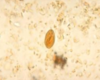

Giardia—cyst

Giardia—cyst

Giardia—cyst